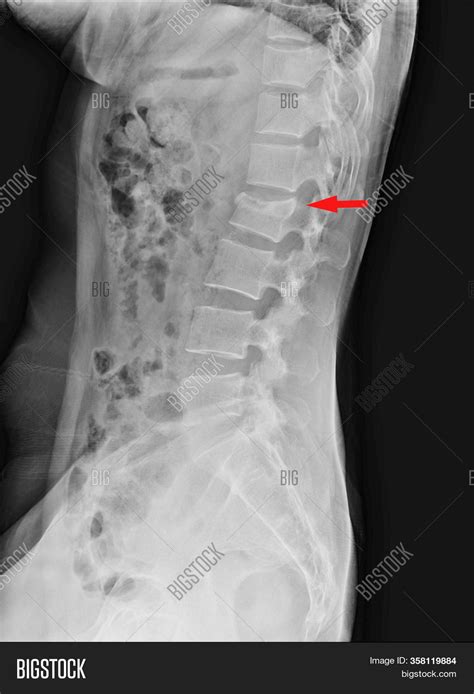

When a technician captures these images, they generally take views from multiple angles—typically an anteroposterior (front-to-back) view and a lateral (side) view. The radiologist then meticulously reviews several specific components of your spine:

• Disc Space Height: While X-rays do not show soft tissue well, the space between the bones can suggest the health of the intervertebral discs. A “normal” space suggests no severe narrowing.

• Vertebral Body Integrity: Checking for any compression fractures or structural changes.

Common Findings in a Diagnostic Report

It is common for patients to feel confused when reading their report. Even if a report is considered “normal,” you might see medical terminology that seems intimidating. A Normal X Ray Ls Spine does not always mean a “perfect” spine; it means there are no pathological findings that require immediate intervention.

Understanding Radiological “Incidentalomas”

Sometimes, an X-ray might pick up something that is technically “abnormal” but completely unrelated to your current pain. These are often referred to as incidental findings. Because the human spine is subject to years of wear and tear, it is extremely rare for an adult to have a “perfect” spine. You might see terms like “minor osteophyte formation” or “mild degenerative changes.” In many cases, these are considered normal aging processes rather than the specific cause of your acute pain. Your doctor will weigh these minor findings against your clinical examination to determine if they are clinically relevant.